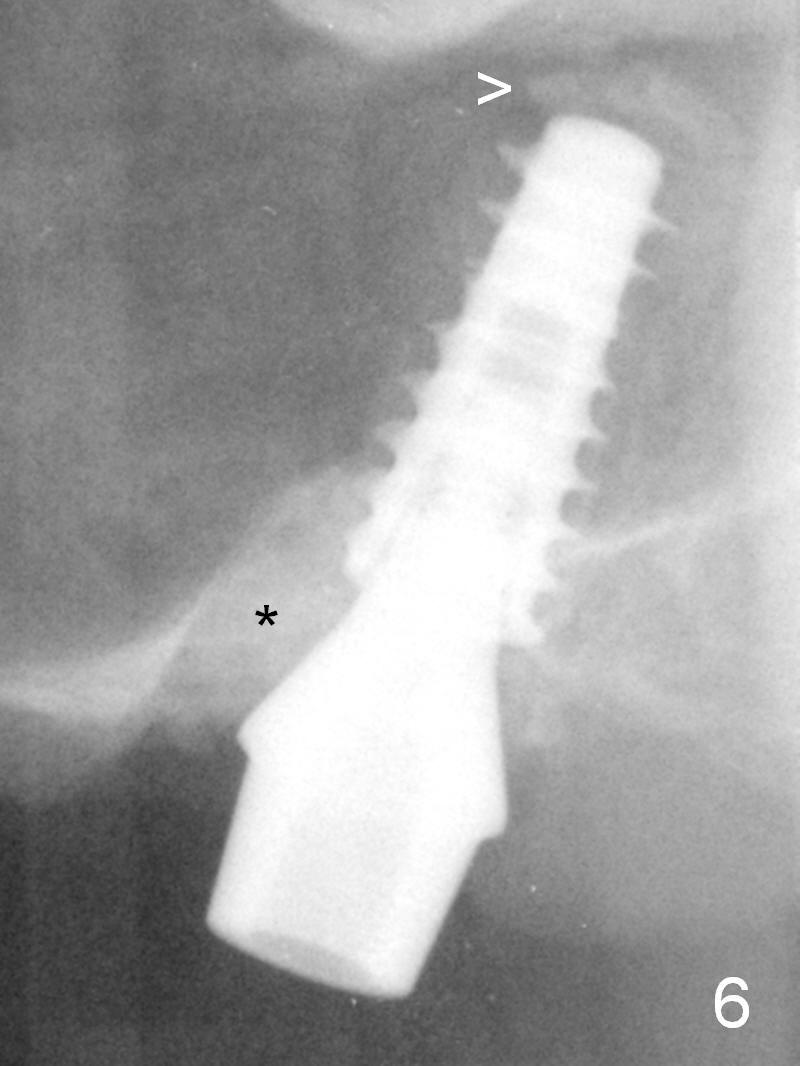

After placing allograft for sinus lift (Fig.6 >), a 5x11 mm IBS implant is placed with insertion torque ~ 50 Ncm.  A 6x4(3) mm pair abutment is placed, followed by bone graft in the remaining sockets (*).